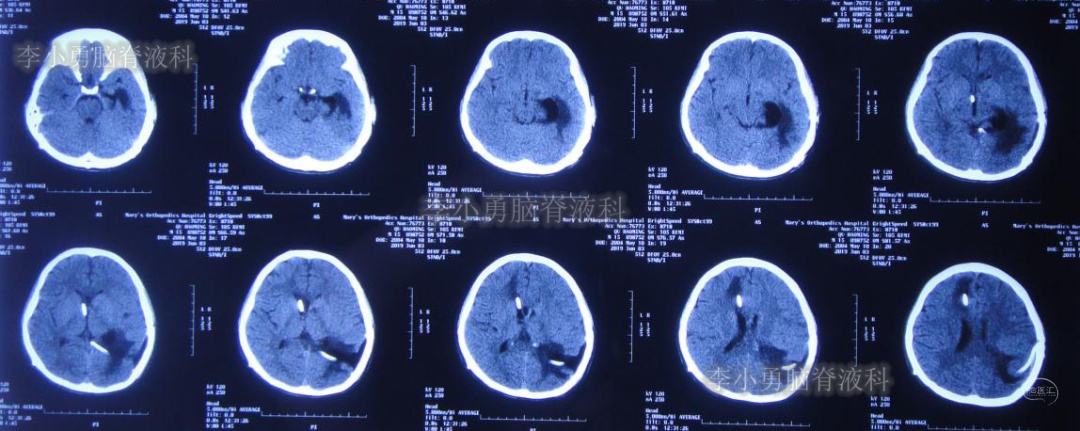

入院当日行头颅CT(图-10):脑室内“动脉瘤切除术”后改变,术区可见引流管影,脑室扩大。

图-10:2019年5月7日头颅CT:引流术后,脑室扩大

入院次日即2019年5月8日,进行了右侧脑室外引流术,并保留原来脑室外引流管(注:脑室内有两根管)。术后常规复查头颅CT(图-11)。

图-11:2019年5月9日头颅CT:引流出淡黄色脑脊液

图-12:2019年5月16日复查头颅CT:左侧颞角扩大并周边水肿

图-14:2019年5月28日头颅CT:脑室较前缩小,水肿亦减轻

但是患者逐渐开始出现头部不适,轻度头痛,且近期记忆力很差。右侧脑室外引流术后25天即2019年6月3日,再次复查头颅CT(图-15):右侧颞角再次扩大并周边水肿明显,术区水肿。

图-15:2019年6月3日头颅CT:左侧颞角扩大并周围水肿